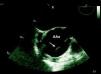

The patient had a history of hypertension, irregularly treated, type 2 diabetes and previous smoking (35 pack/years). He had been experiencing progressively worsening fatigue and exertional dyspnea for a year. The present hospitalization was prompted by thoracic and epigastric pain radiating to the back accompanied by dyspnea, with one day of evolution. Physical observation revealed hypertension and a grade IV/VI aortic diastolic murmur. Initial laboratory tests and electrocardiogram were normal. Transthoracic echocardiography showed marked dilatation of the aortic root and ascending aorta (maximum transverse diameter 71mm) with severe aortic regurgitation. An image suggestive of an intimal flap prompted assessment by transesophageal echocardiography, which confirmed an aneurysmal dilatation of the aortic root and ascending aorta (maximum transverse diameter 71mm) sparing the aortic arch and the descending aorta. The aortic valve was tricuspid and severe regurgitation was seen, due to malcoaptation of the leaflets. A linear image moving relative to the right coronary sinus, suggestive of an intimal flap, was observed, which could have corresponded to the course of a dissection (Figs. 1 and 2). Thoracic computed tomography performed at the original hospital confirmed aortic dilatation but appeared to exclude dissection or rupture.

On admission to our hospital the patient was asymptomatic, under therapy with nitrates and beta-blockers and hemodynamically stable. Cardiac magnetic resonance imaging revealed aneurysmal dilatation limited to the aortic root and ascending aorta (maximum transverse diameter 65mm) and excluded dissection or rupture (Figs. 3 and 4). Preoperative cardiac catheterization excluded coronary disease and aortography, performed at the same time, documented annulo-aortic ectasia (maximum transverse diameter of the ascending aorta 75mm) (Fig. 5). The patient underwent a Bentall procedure, a 25-mm Carpentier–Edwards aortic valve and a 28-mm Vascutek tube graft being implanted. The postoperative course was uneventful and the patient was discharged five days later. Anatomopathological analysis of the resected arterial wall showed numerous atherosclerotic plaques with focal ulceration.